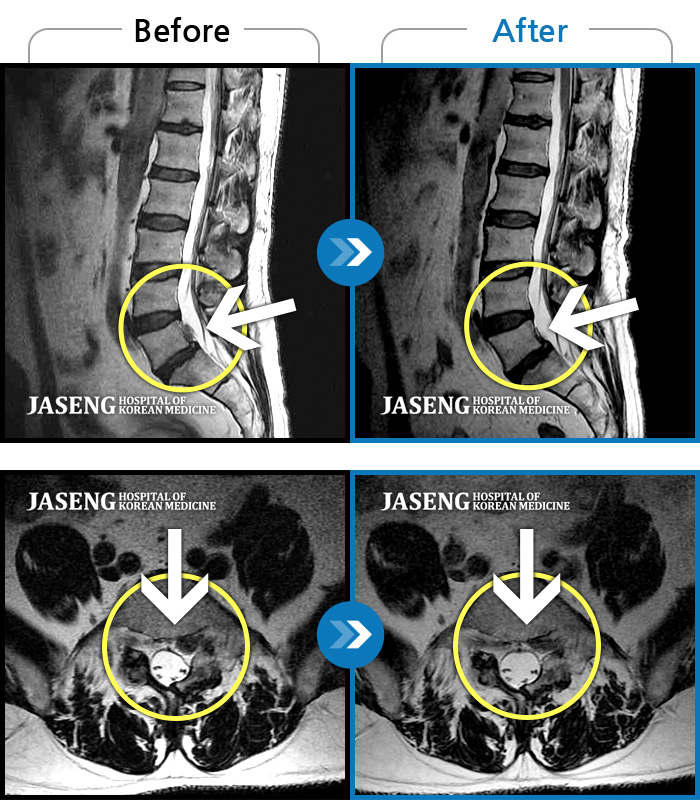

MRI 치료사례

엉치에서 좌측 다리 뒤쪽으로 통증과 저림이 매우 심해요.